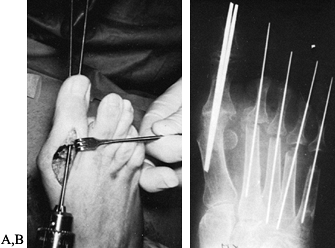

hammer-toe and claw-toe deformities that occur in association with MTP

fixation (closed osteoclasis) (14,23,49,60,70), more severe deformities need a proximal phalangeal condylectomy to achieve realignment with bony decompression (22,23,43,49,95).

Center an elliptical incision over the dorsal proximal interphalangeal (PIP) joint of the lesser toe (Fig. 117.6). Excise the dorsal callus, extensor tendon, and joint capsule, exposing the PIP joint.

Figure 117.6. Hammer-toe repair. A: Resection of the distal condyle of the proximal phalanx. B: Use of an intramedullary K-wire to stabilize the arthroplasty site. -

Following metatarsal head resection, correct hammer-toe deformities with a closed osteoclasis or an open hammer-toe repair (see Chapter 113). Introduce an 0.045 K-wire at the PIP joint and drive it in a distal direction to exit the tip of the toe (Fig. 117.9C). Advance it proximally into the metatarsal diaphyses and metaphyses.